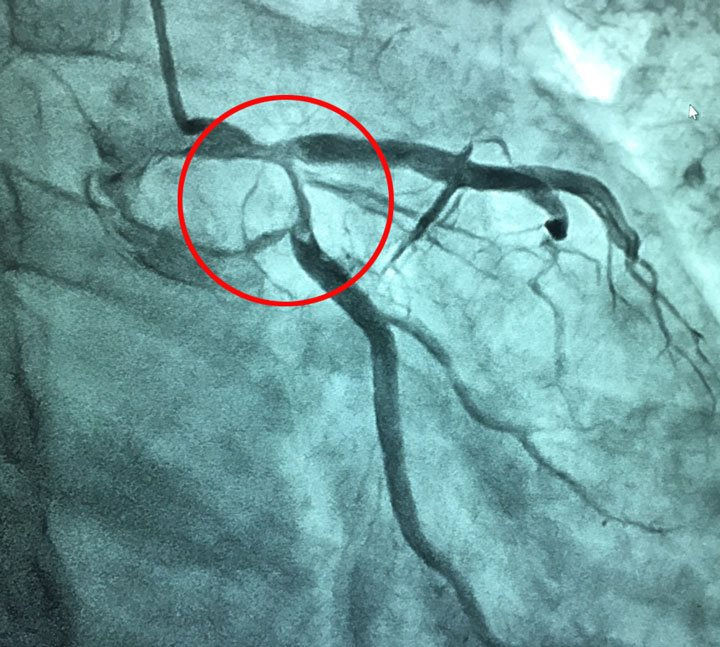

Hình ảnh tắc mạch của người bệnh trước can thiệp (vùng khoanh tròn màu đỏ)

Người bệnh được chẩn đoán: Nhồi máu cơ tim cấp/đa hồng cầu, được nhanh chóng chuyển phòng can thiệp tim mạch chụp mạch vành, kết quả huyết khối trên nền mảng xơ vữa gây bán tắc động mạch mũ, đã được can thiệp hút huyết khối và đặt stent.